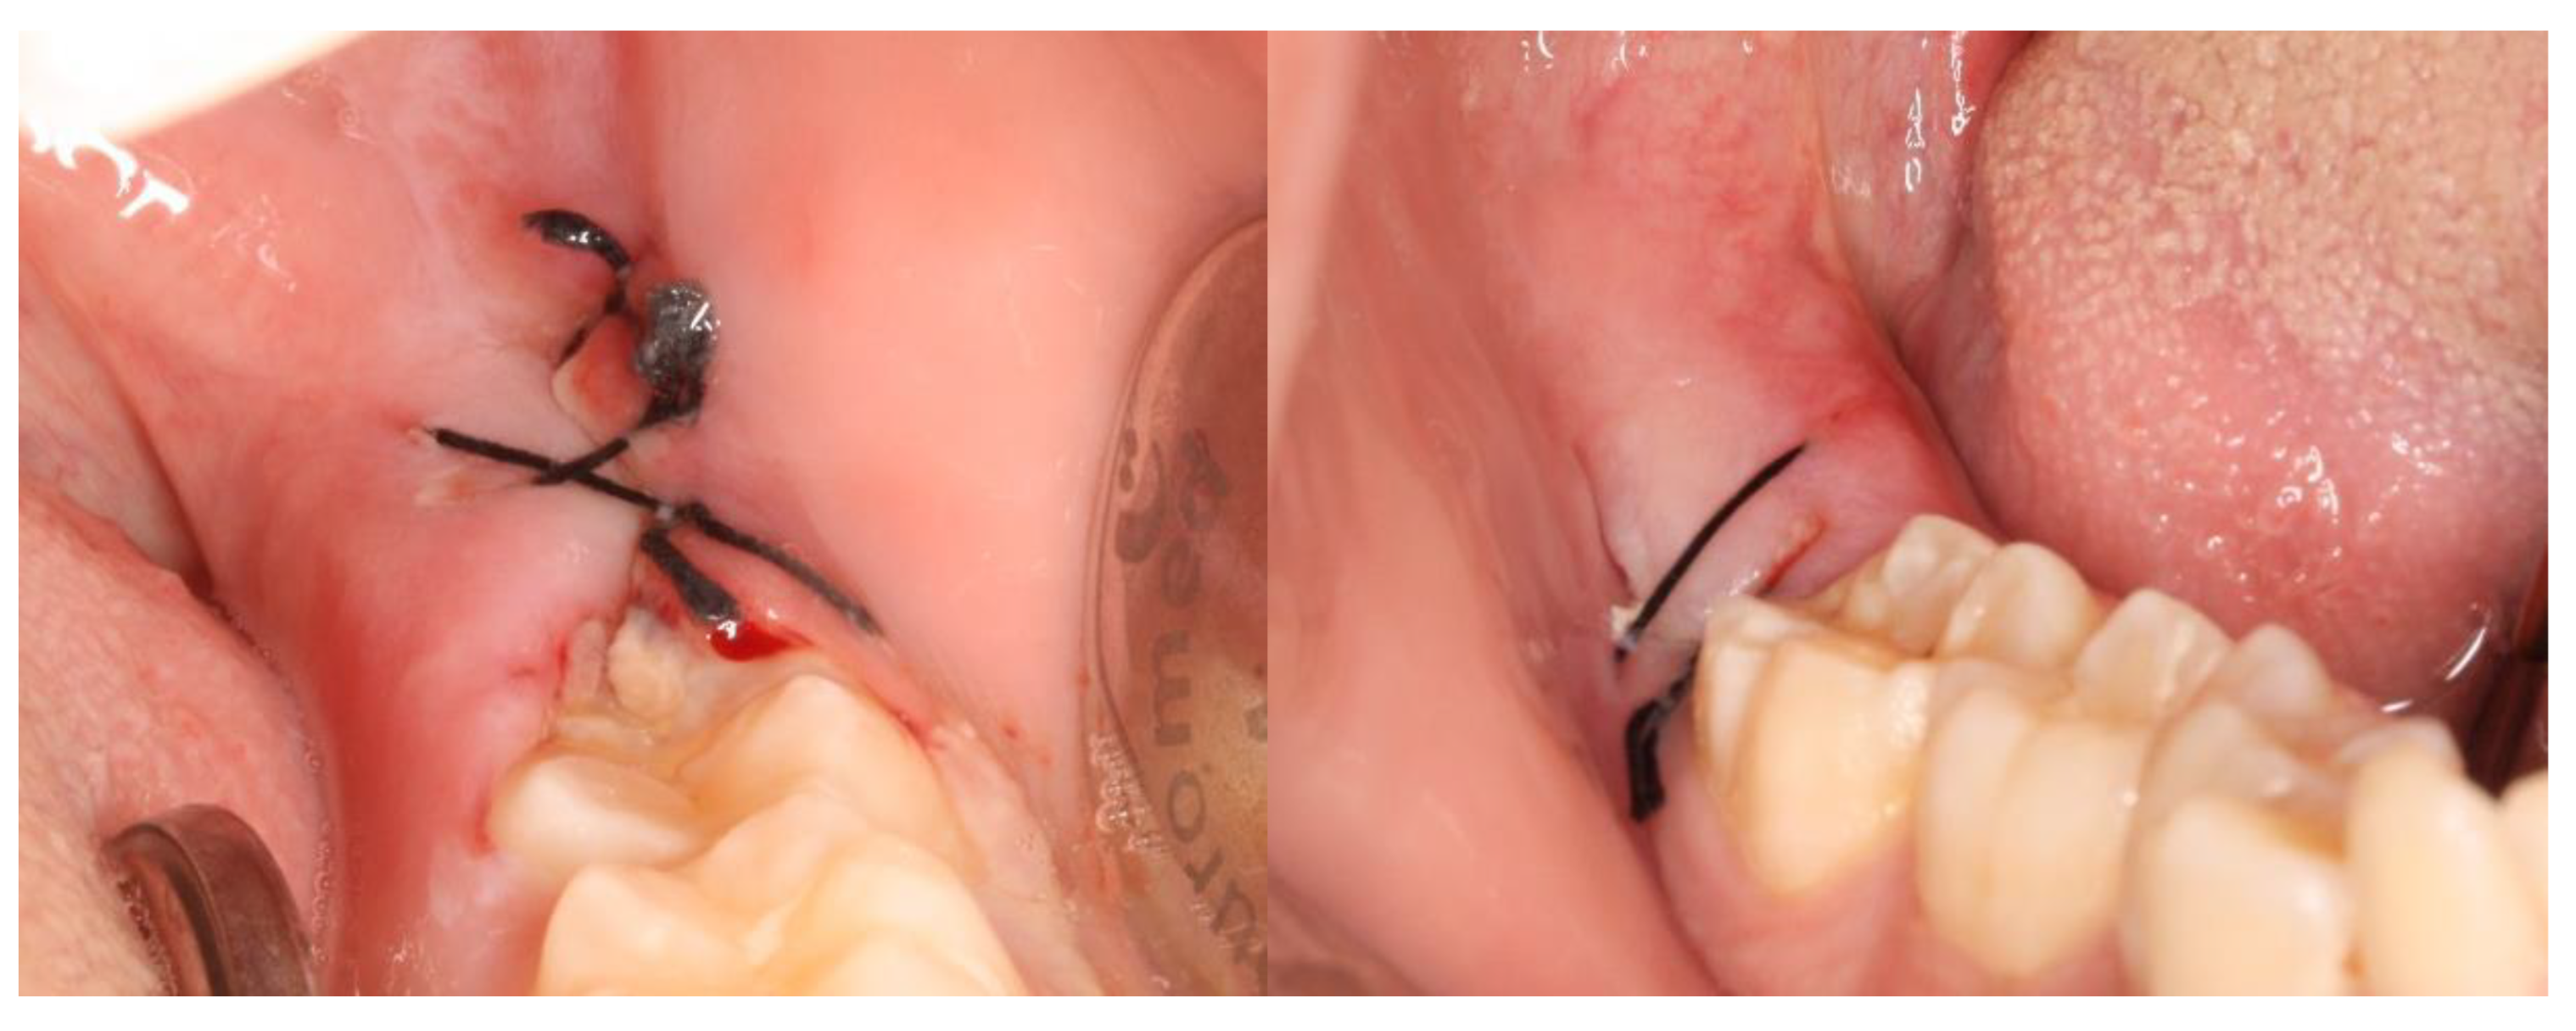

2.2. Definition of the Variables in Study and Follow-Up of Patients

3. Results